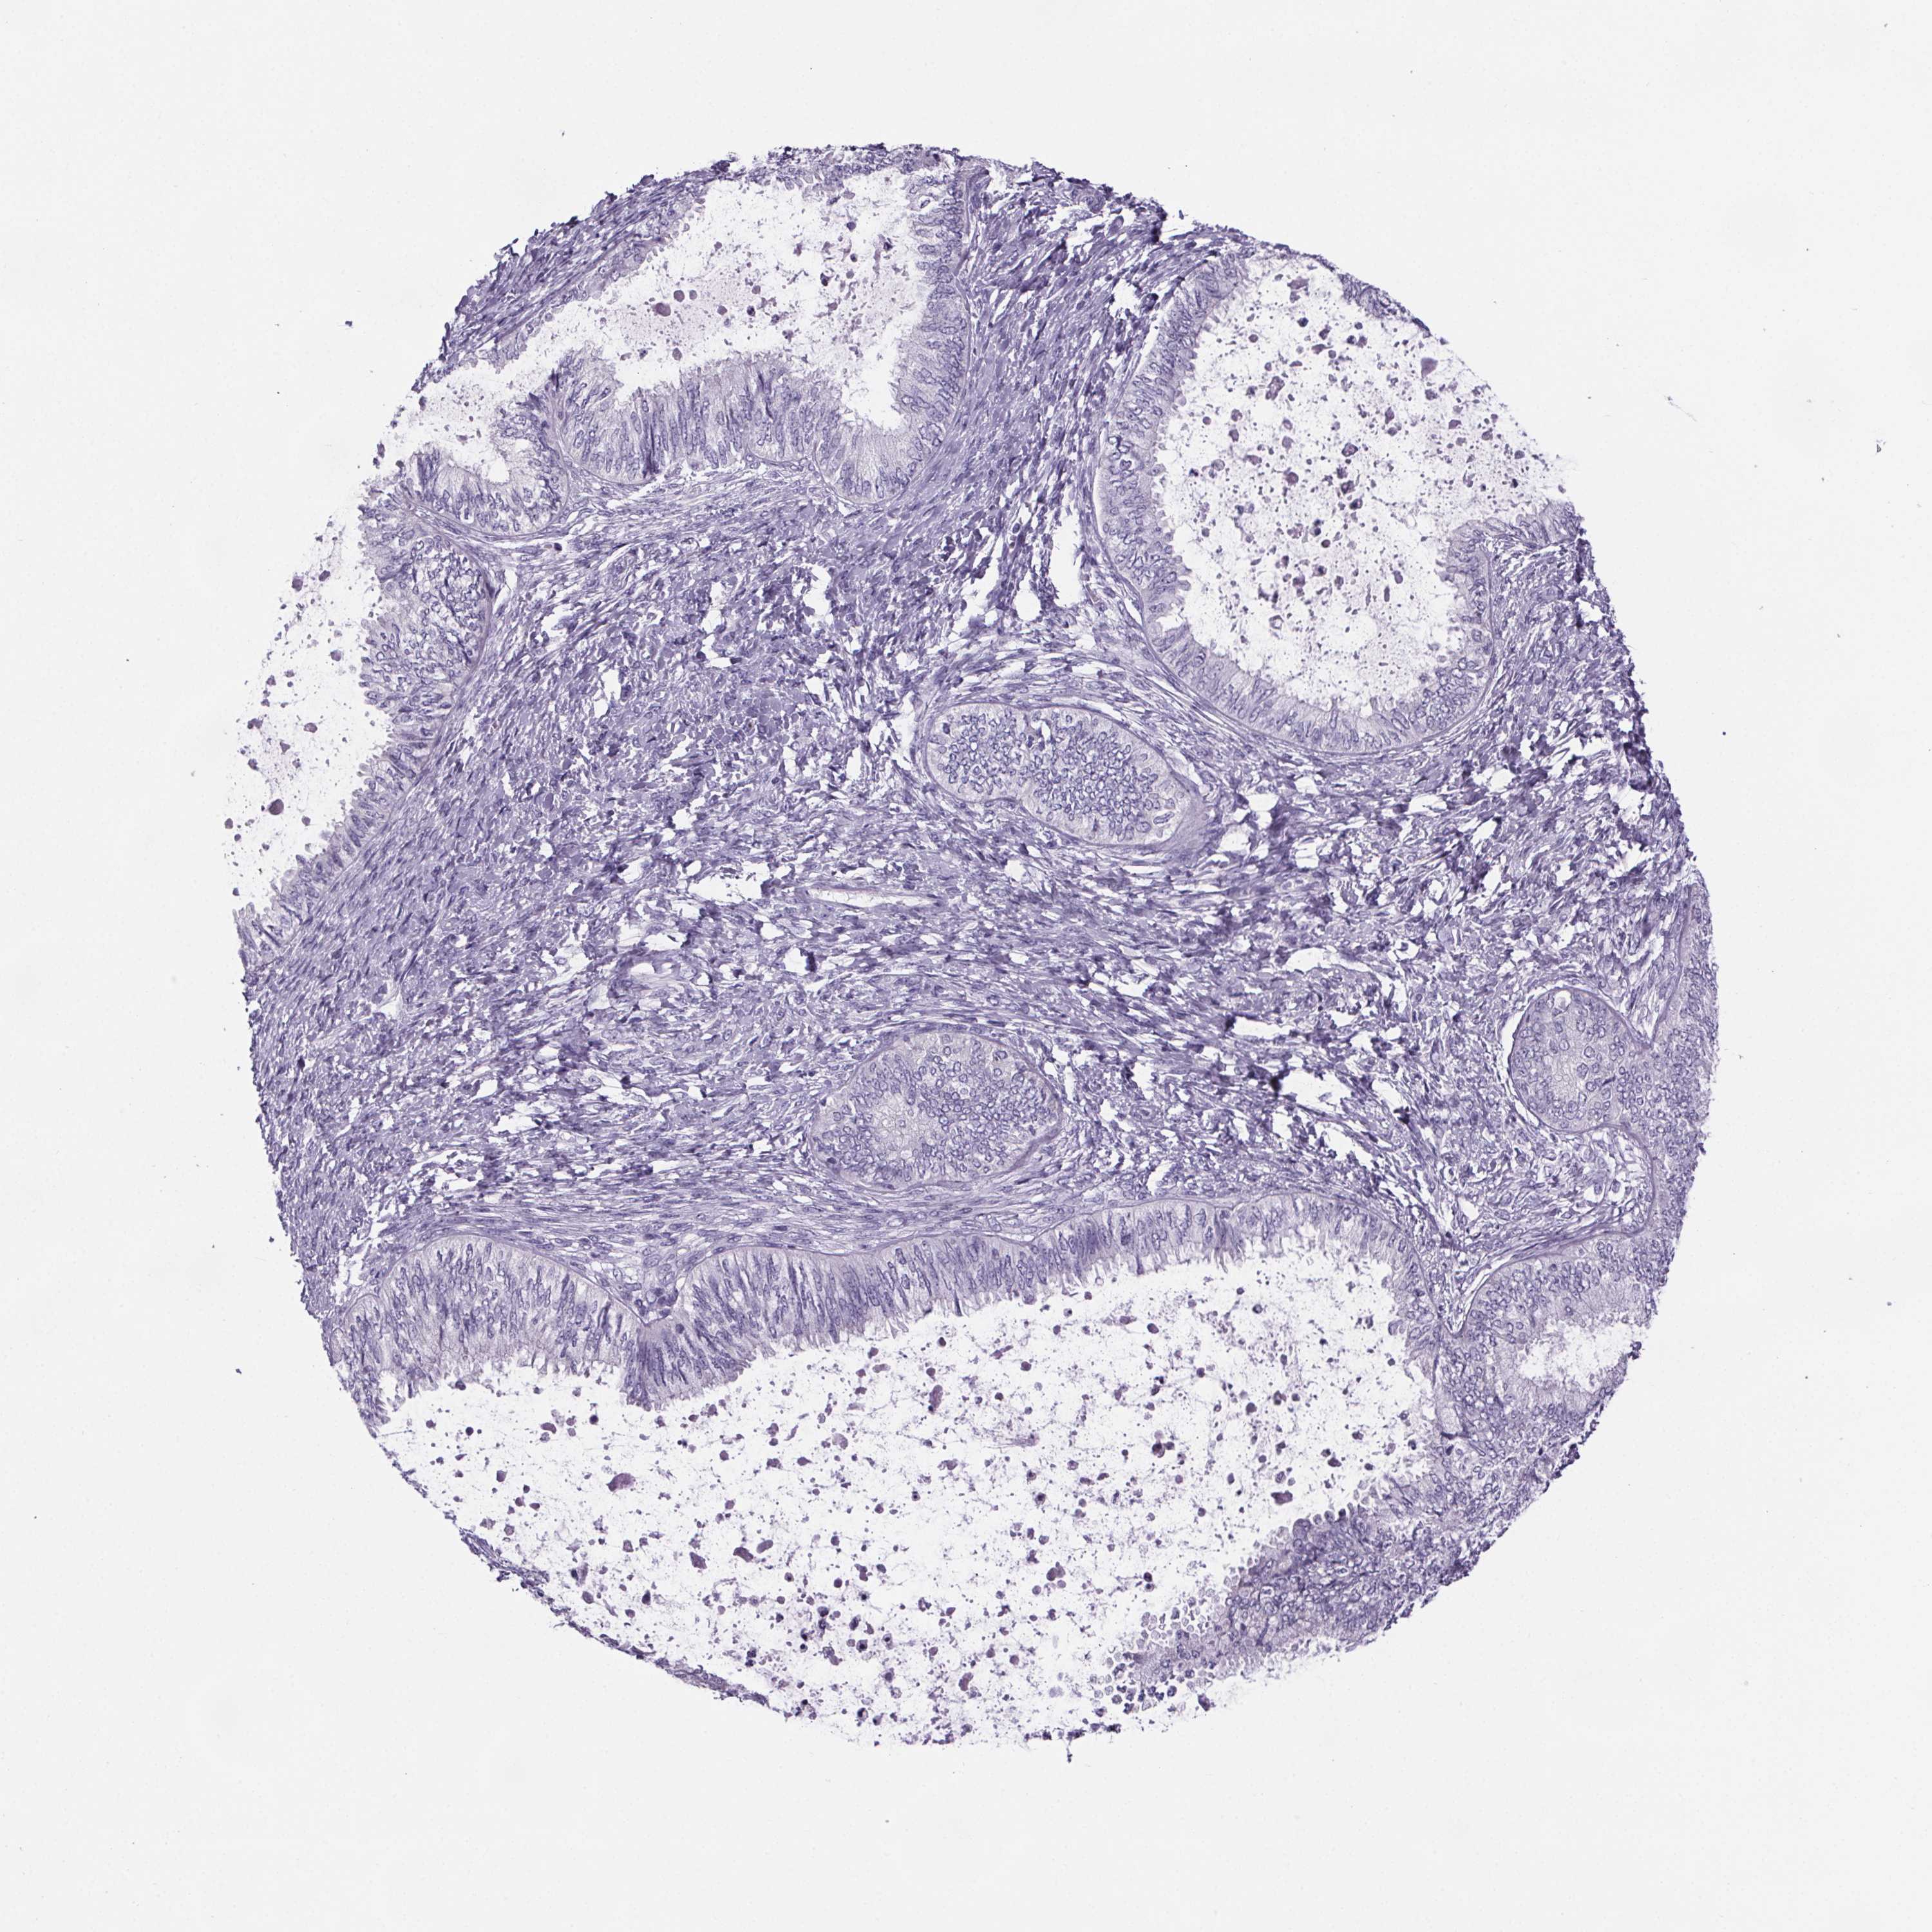

OVARIAN CANCER - Protein expressioni

A mouse-over function shows sample information and annotation data. Click on an image to view it in a full screen mode. Samples can be filtered based on level of antibody staining by selecting one or several of the following categories: high, medium, low and not detected. The assay and annotation is described here.

Note that samples used for immunohistochemistry by the Human Protein Atlas do not correspond to samples in the TCGA dataset.

Antibody stainingi

Antibody staining in the annotated cell types in the current human tissue is reported as not detected, low, medium, or high, based on conventional immunohistochemistry profiling in selected tissues. This score is based on the combination of the staining intensity and fraction of stained cells.

Each image is clickable and will lead to virtual microscopy that enables deeper exploration of all samples and also displays staining intensity scores, fraction scores and subcellular localization as well as patient and tissue information for each sample.

Antibody HPA004133

Antibody HPA043854

Cystadenocarcinoma, serous, NOS

Cystadenocarcinoma, mucinous, NOS

Carcinoma, endometroid